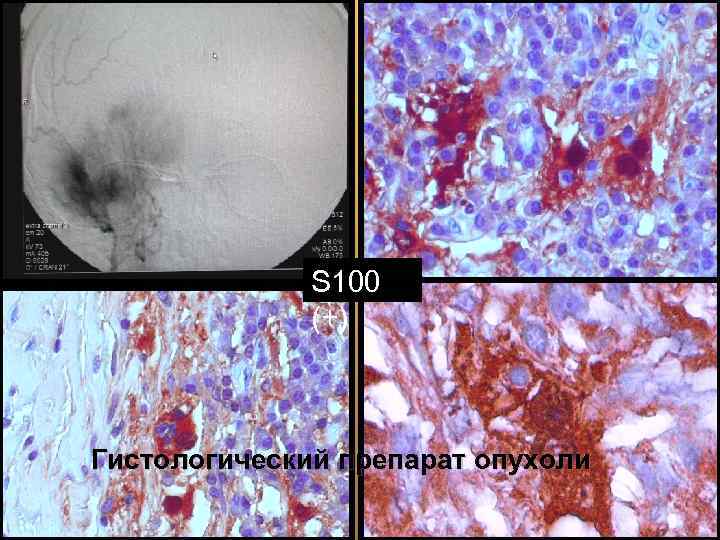

S 100 (+) Гистологический препарат опухоли 56